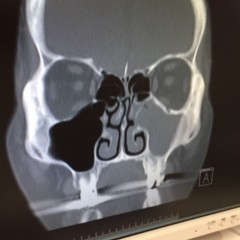

これ、私の顔面写真ですが、分かりますかね?右頬が埋まってるのが‥

蓄膿症らしいです。まったく症状が出ないと言うか分からなかったんですが、医師がこれは早めに手術だよと